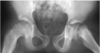

Q

Dx?

A

Legg-Calve Perthes disease